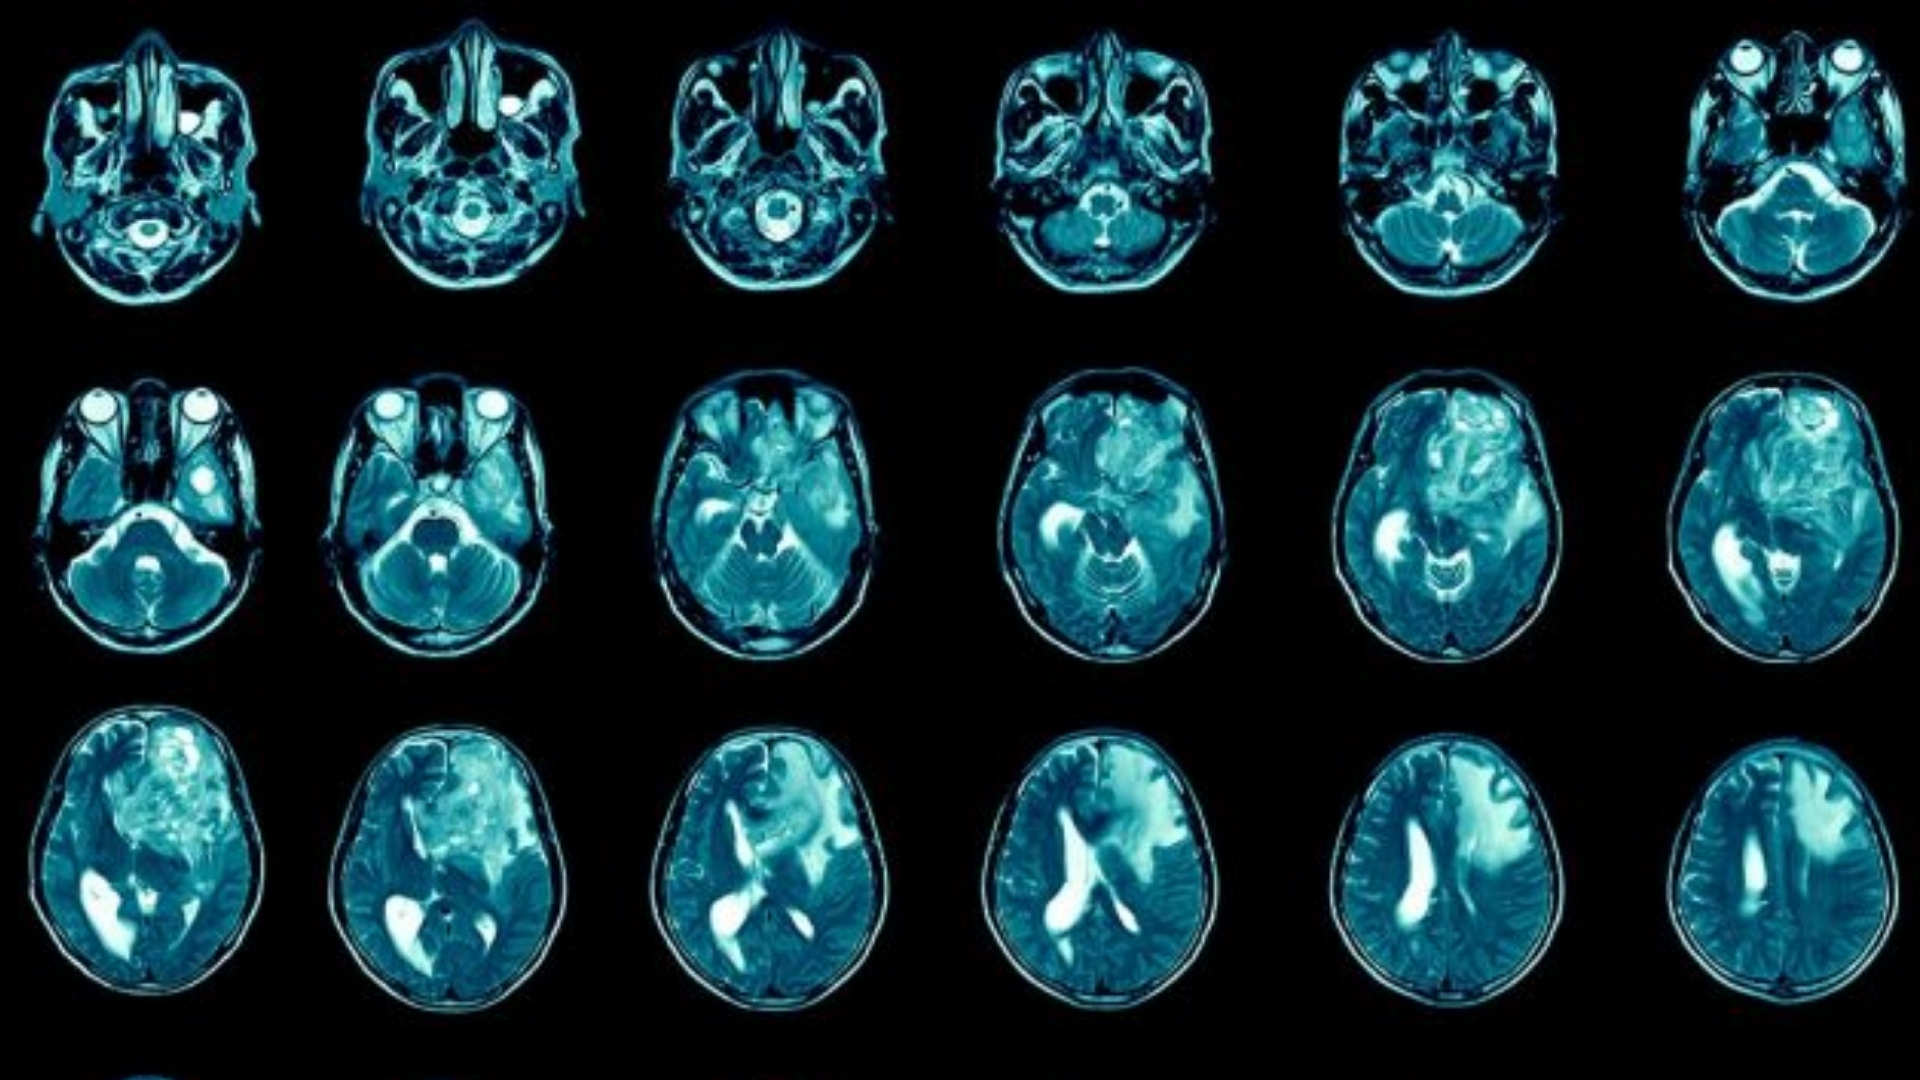

膠質母細胞瘤 (GBM) 是最具侵襲性的原發性腦癌,起源於膠質細胞 - 神經元周圍的支持性組織。Glioblastoma (GBM) 腫瘤的特徵是細胞快速增殖和顯著的新陳代謝變化,嚴重依賴葡萄糖新陳代謝。具體來說,GBM 腫瘤細胞呈現沃伯格效應 (Warburg effect),癌細胞的葡萄糖代謝率比正常細胞高出 200 倍,從根本上改變了細胞的能量平衡和增殖。

及早發現症狀可顯著改善膠質母細胞瘤 (GBM) 的預後和治療效果。膠質母細胞瘤 (GBM) 通常會出現腦內位置相關的症狀,通常是由於顱內壓增高和局部組織破壞所致。

膠質母細胞瘤 (GBM) 的症狀與腫瘤的生物學特性和位置直接相關。舉例來說,靠近腦部語言中心的腫瘤通常會造成語言障礙,而靠近運動皮層區域的腫瘤則會造成肌肉無力和行動不便。